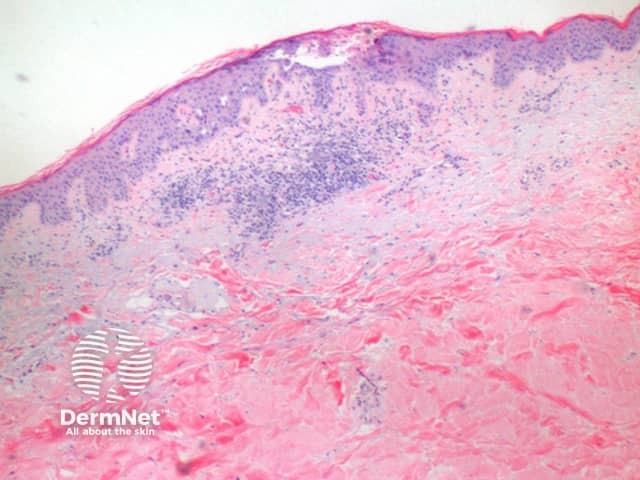

The scanning power view of the histology of Darier disease is of an epidermal and superficial dermal inflammatory process (Figure 1). Intraepidermal separation may be visible at this power, which on closer inspection is seen as suprabasal acantholysis (Figures 2 and 3). Acantholysis can be seen at all levels within the epidermis. Dyskeratosis of the keratinocytes is seen, with two notable changes described. Corps ronds refer to cells with small pyknotic nuclei, a perinuclear clear halo and eosinophilic cytoplasm (Figures 4 and 5).

In the superficial dermis is a mild predominantly perivascular lymphocytic infiltrate (Figure 2). Eosinophils are rarely seen.

Figure 1